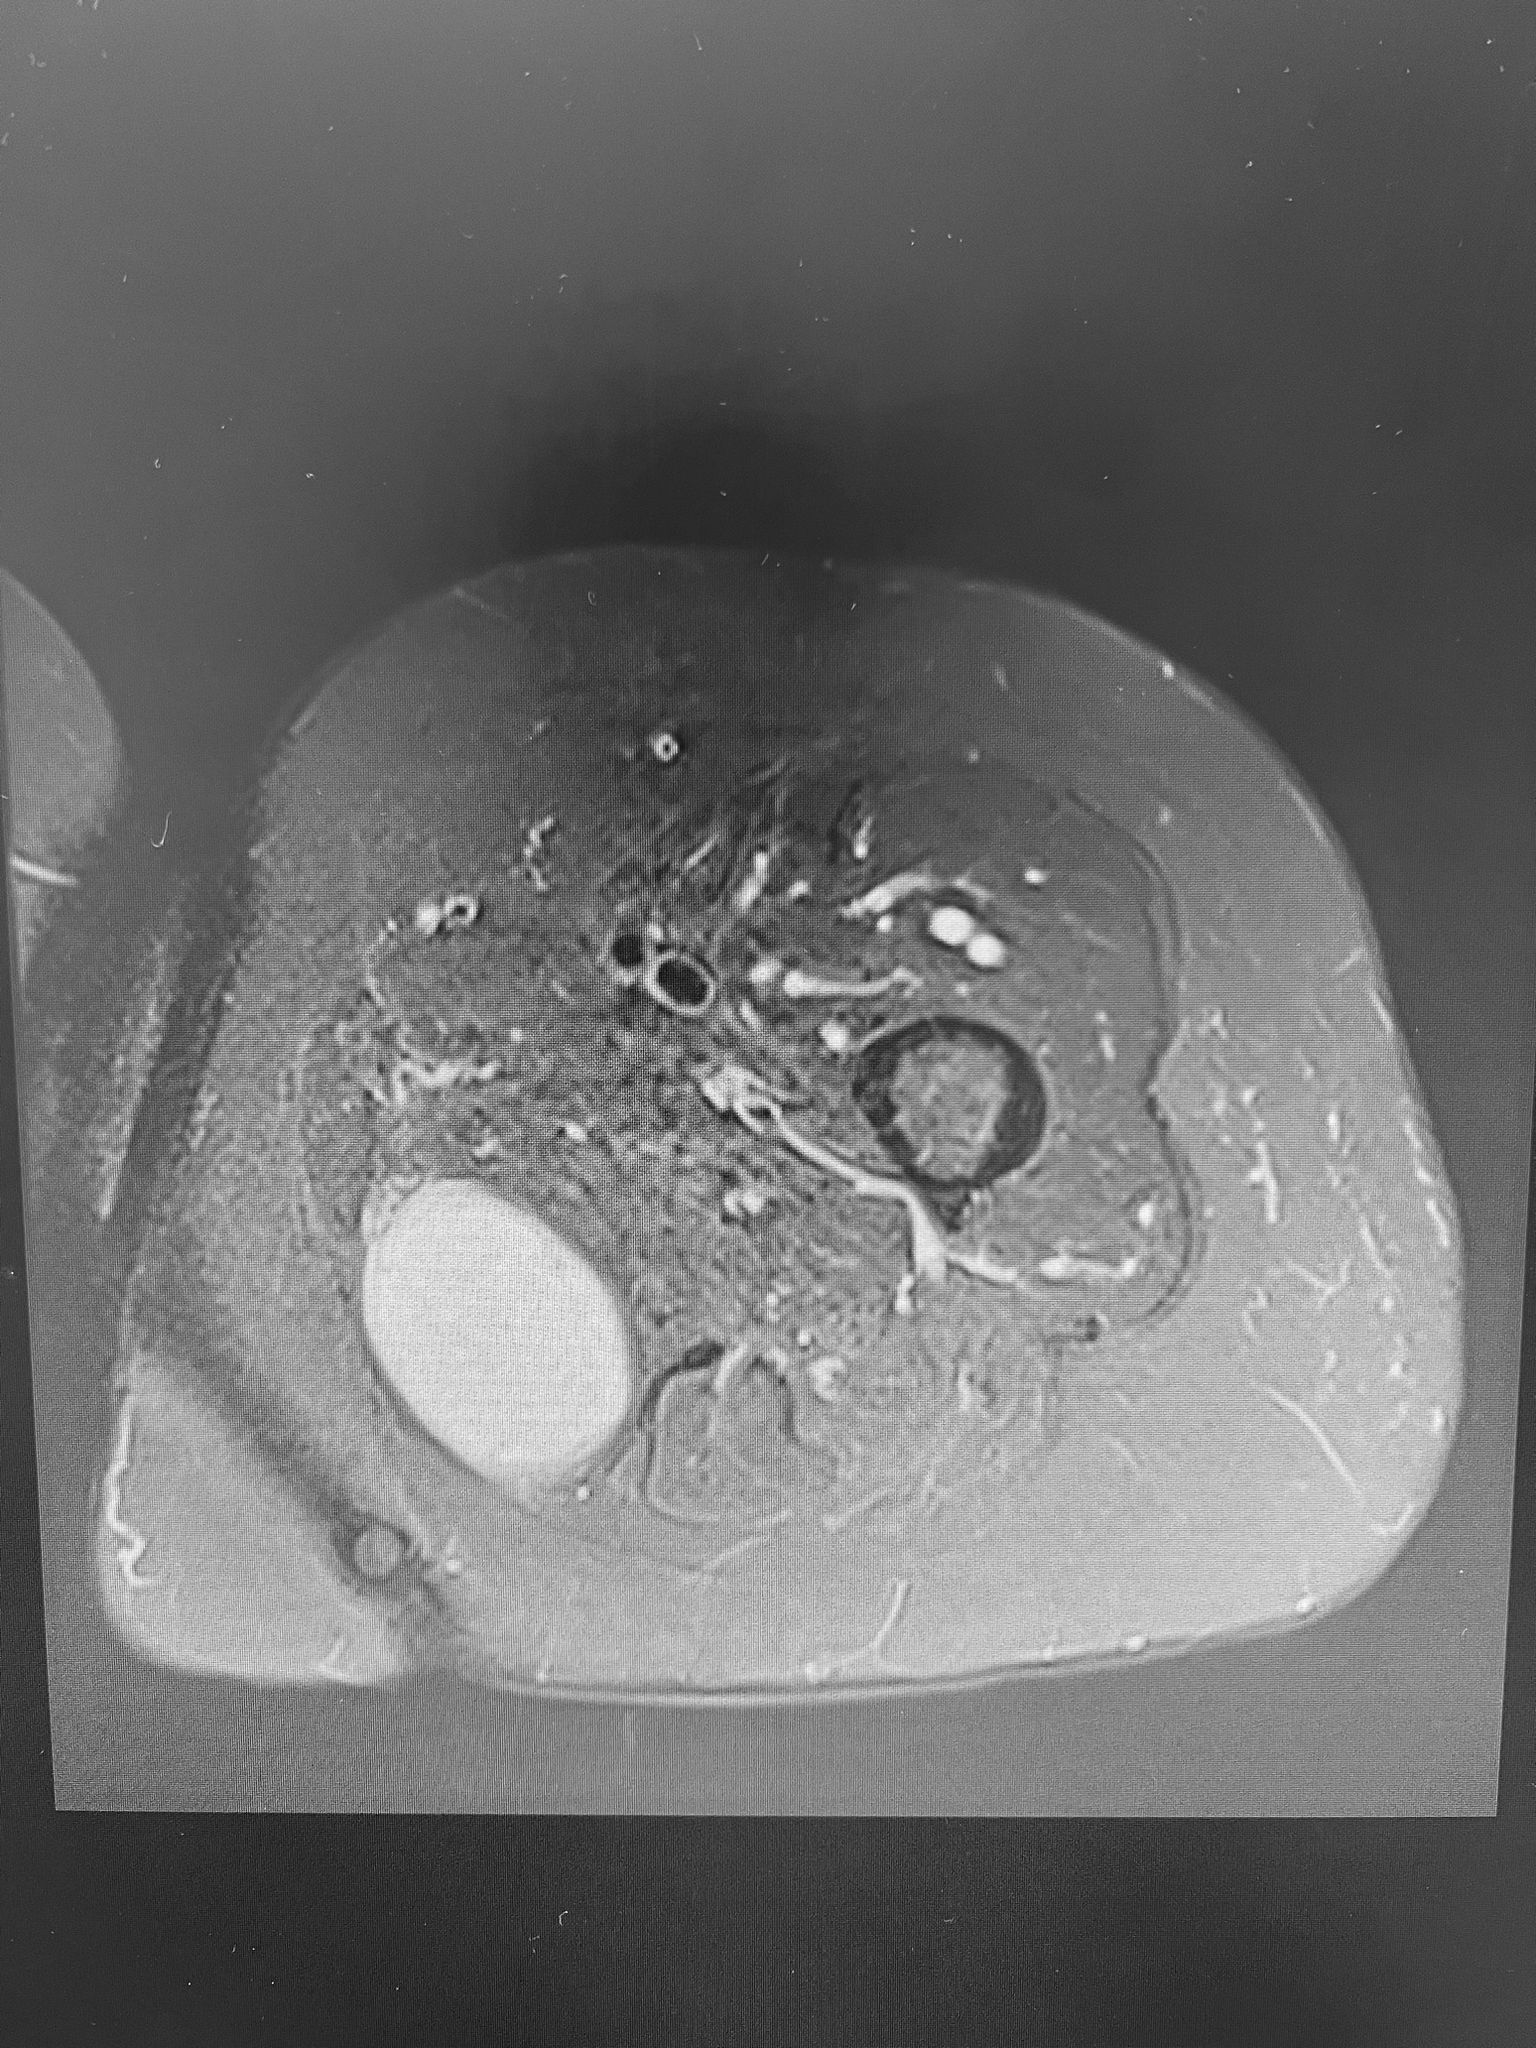

Tumoración de partes blandas en aspecto medial del tercio proximal de muslo izquierdo. Tumoración ovalada de contornos bien definidos, profunda, intramuscular entre las fibras mas posteriores y mediales del aductor mayor.

La tumoración muestra un aspecto multilobulado en T2, sin signos de sangrado ni componente adiposo.

No se aprecia restricción en difusión, todo ello compatible con mixoma.